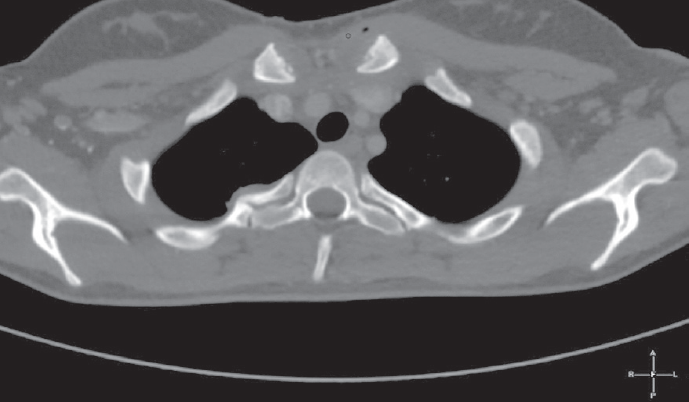

The optimal time for surgery on the heart valves in patients with active infectious endocarditis (IE) is still controversial. It is a well known fact that cerebral, coronary or renal thromboembolism is the most common cause of death in patients with left-sided IE. Thromboembolism can develop before the appearance of clinical manifestations of the destruction of the valvular apparatus of the heart. Currently, early surgical intervention is considered as the most effective method of treatment of many forms of active left-sided IE. Early surgery involves performing surgical correction until the completion of a full antibiotics course. We present the clinical case of early surgical correction of the patient (A., 16 years) with mitral valve infectious endocarditis. The disease was acute, with recurrent embolisms to the right kidney with infarction and to the left clavicle with osteomyelitis. Surgical intervention was performed as a matter of urgency; surgical access – right-sided anterolateral thoracotomy. The girl was operated on the 4th day of the hospitalization to our hospital. However, time of treatment was lost at the prehospital stage and rapid mitral valve destruction did not allow to repair the valve. Therefore, the mitral valve replacement was performed. The postoperative period was favorable. On the 3rd day after the operation, the girl was transferred to the cardiology department. On control ECHO after 3 years: myocardial contractile function is good, EF 65%, the function of the MV prosthesis is not impaired.